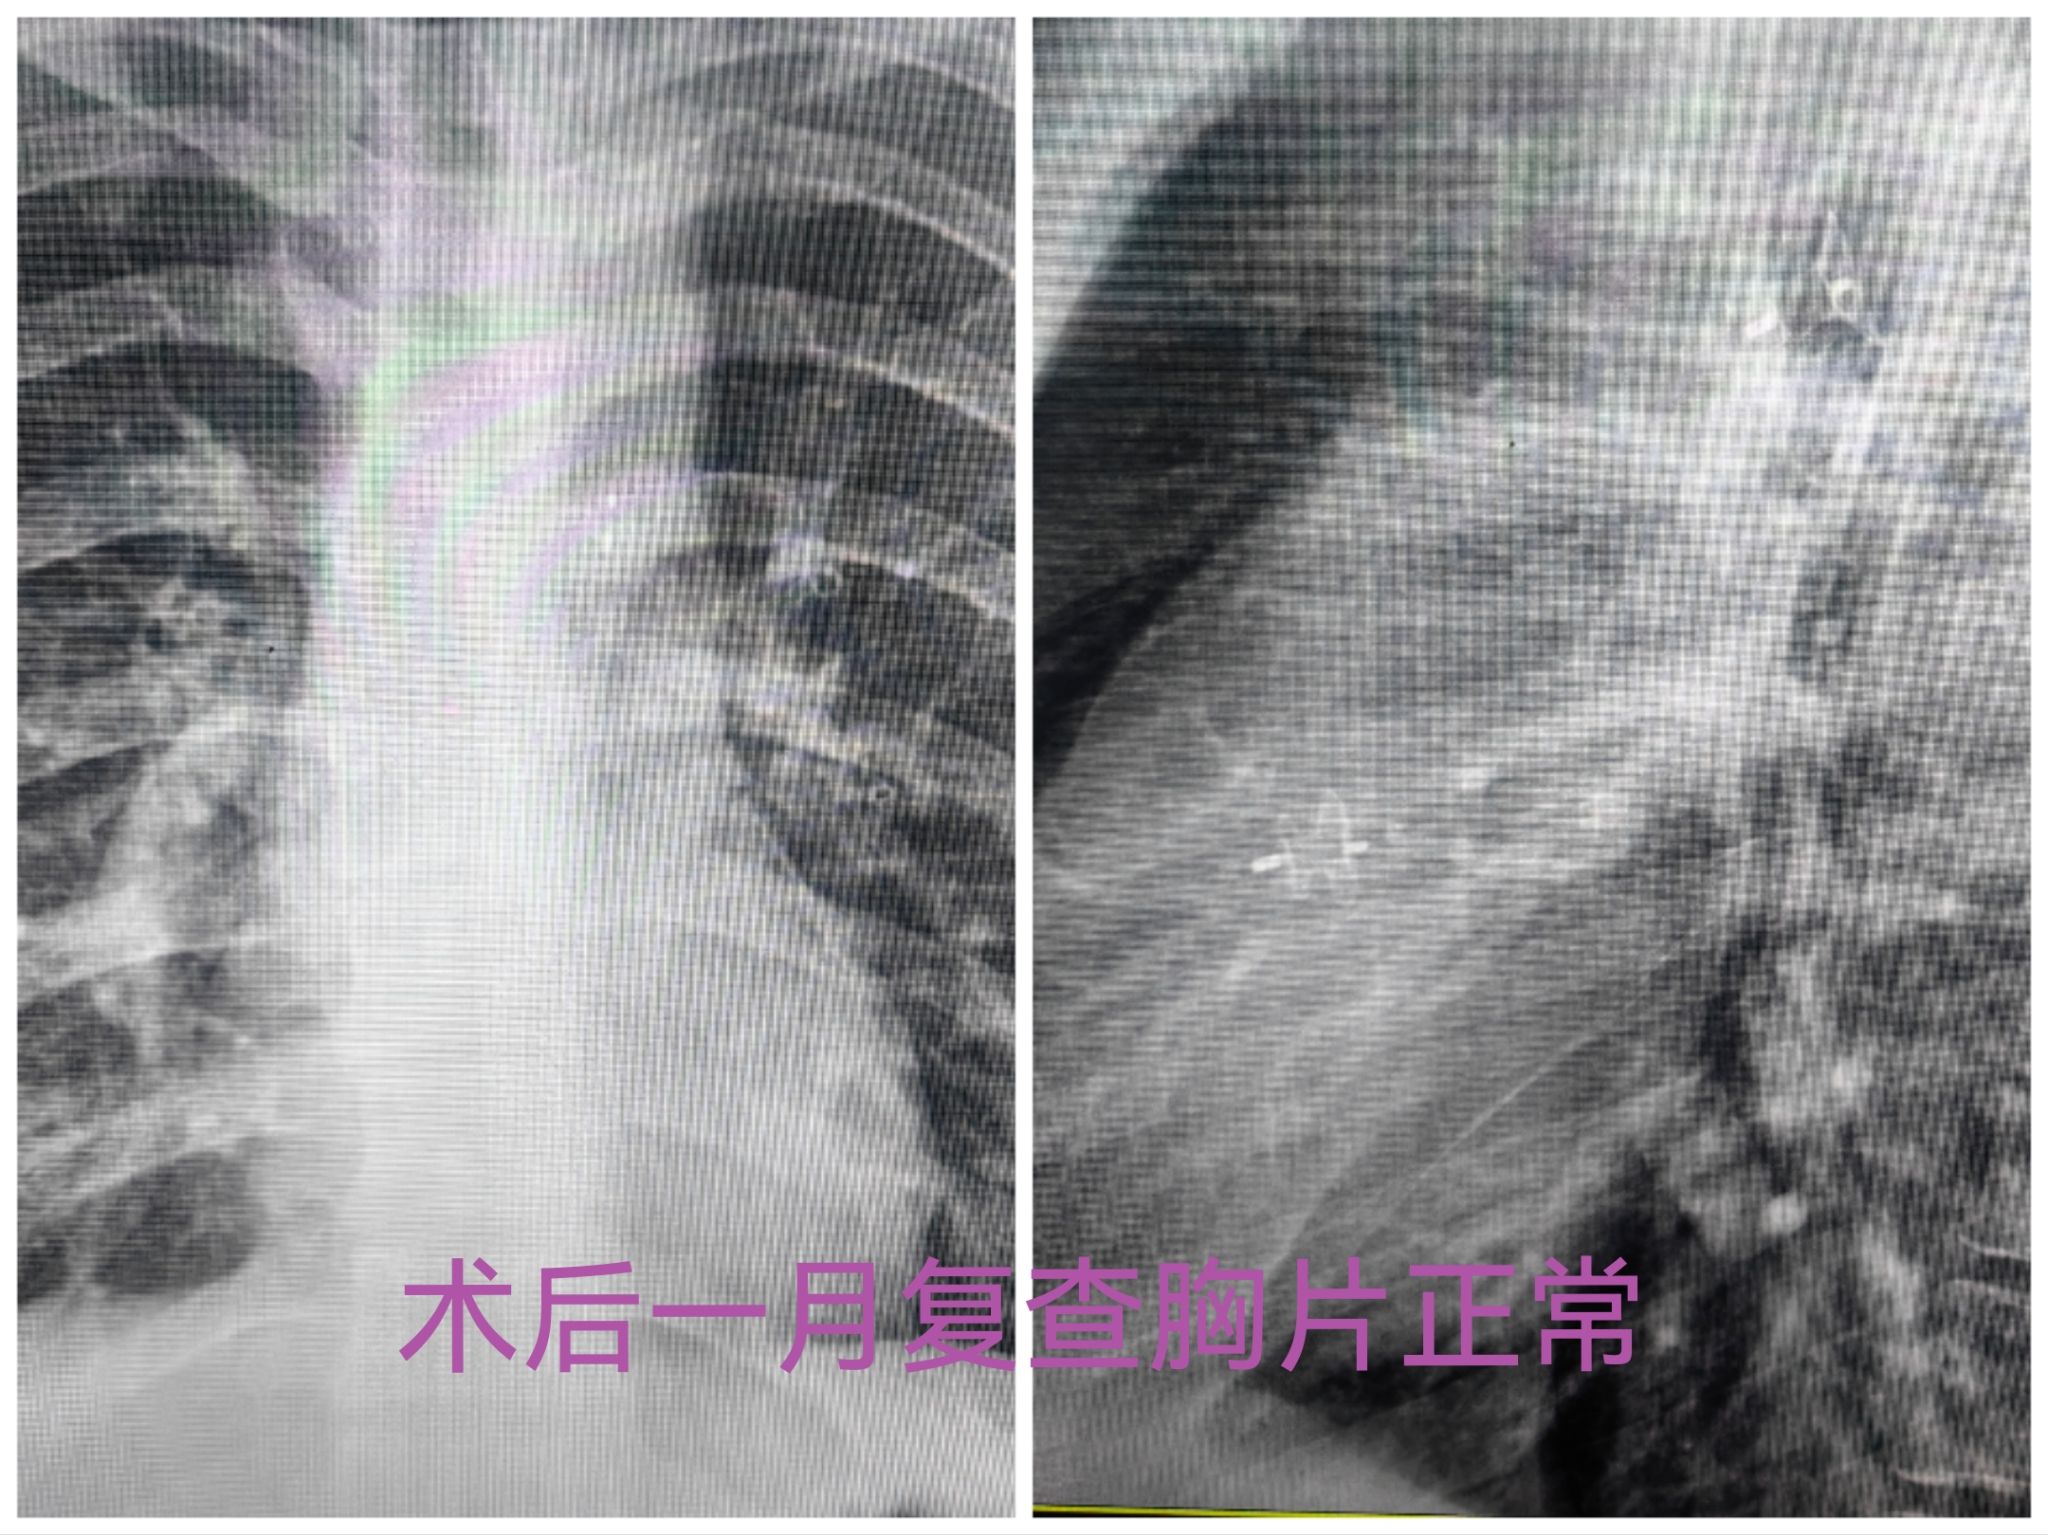

第一次经皮动脉导管未闭封堵手术完成很顺利,在抗凝临床药师季美汐的协助下,手术期间患者凝血功能控制良好,局麻下不到一小时的封堵手术出血仅10ml,术后第二天即出院。在一期手术后闫女士和孩子定期来院复诊,检查结果甚至比预期的更令人满意。中度肺动脉高压逆转下降为轻度,心脏形态较前缩小,三尖瓣反流也明显减少。良好的术后改变给了医患双方极大的信心,在一期术后半年患者再次入住心血管外科,按照计划再次手术矫正其余心脏畸形。考虑到二期术前心脏恢复情况超出预期,再次全面评估患者心脏病变后,相里伟医生提出改变原计划外科手术方式而先尝试用介入封堵治疗室间隔缺损的方案。尽管介入治疗有明显的微创优势,但根据术前影像学检查评估,室间隔缺损同三尖瓣关系密切,可能封堵会影响三尖瓣功能导致手术失败,仍然需要再次外科手术,会增加医疗费用和损伤风险。令人欣慰的是,当谈及介入手术的顾虑时,患者和家属毫不迟疑的选择了信任。如同术前所预料,二期手术中遇到技术和耐心的极大挑战,心室内的假腱索导致输送轨道建立困难,右心室对于刺激极其敏感,室性心律发作频繁多次不得不暂时中断操作,周边组织结构复杂导致封堵器大小的艰难选择等,当诸多障碍被一一克服,当封堵器完全释放后,术中超声证实室间隔水平异常分流完全消失,临近瓣膜的功能不受影响,心脏搏动保持正常节律,介入封堵手术获得成功,身着数十斤铅衣的相里伟和张忆雯两位医生的努力得到了最好的结果。当好消息在第一时间传到手术室外焦急等待的家属时,闫女士难以抑制自己复杂的心情,热泪盈眶无语成咽。术后的事情简单有序,第二天正常恢复日常活动,复查各项检查和凝血指标都正常,三天留院观察后,历时六个月的两次心脏手术治疗达到了安全、极简和经济的完美结局。